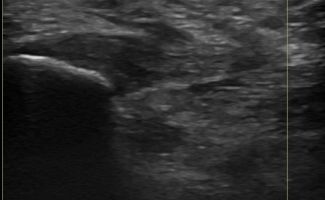

Foot Tendons

Foot Ultrasound allows the diagnosis of tendonitis, tenosynovitis, and rupture in the following tendons:

- Achilles Tendon

- Peroneal Tendons

- Flexor Tendons

- Extensor Tendons